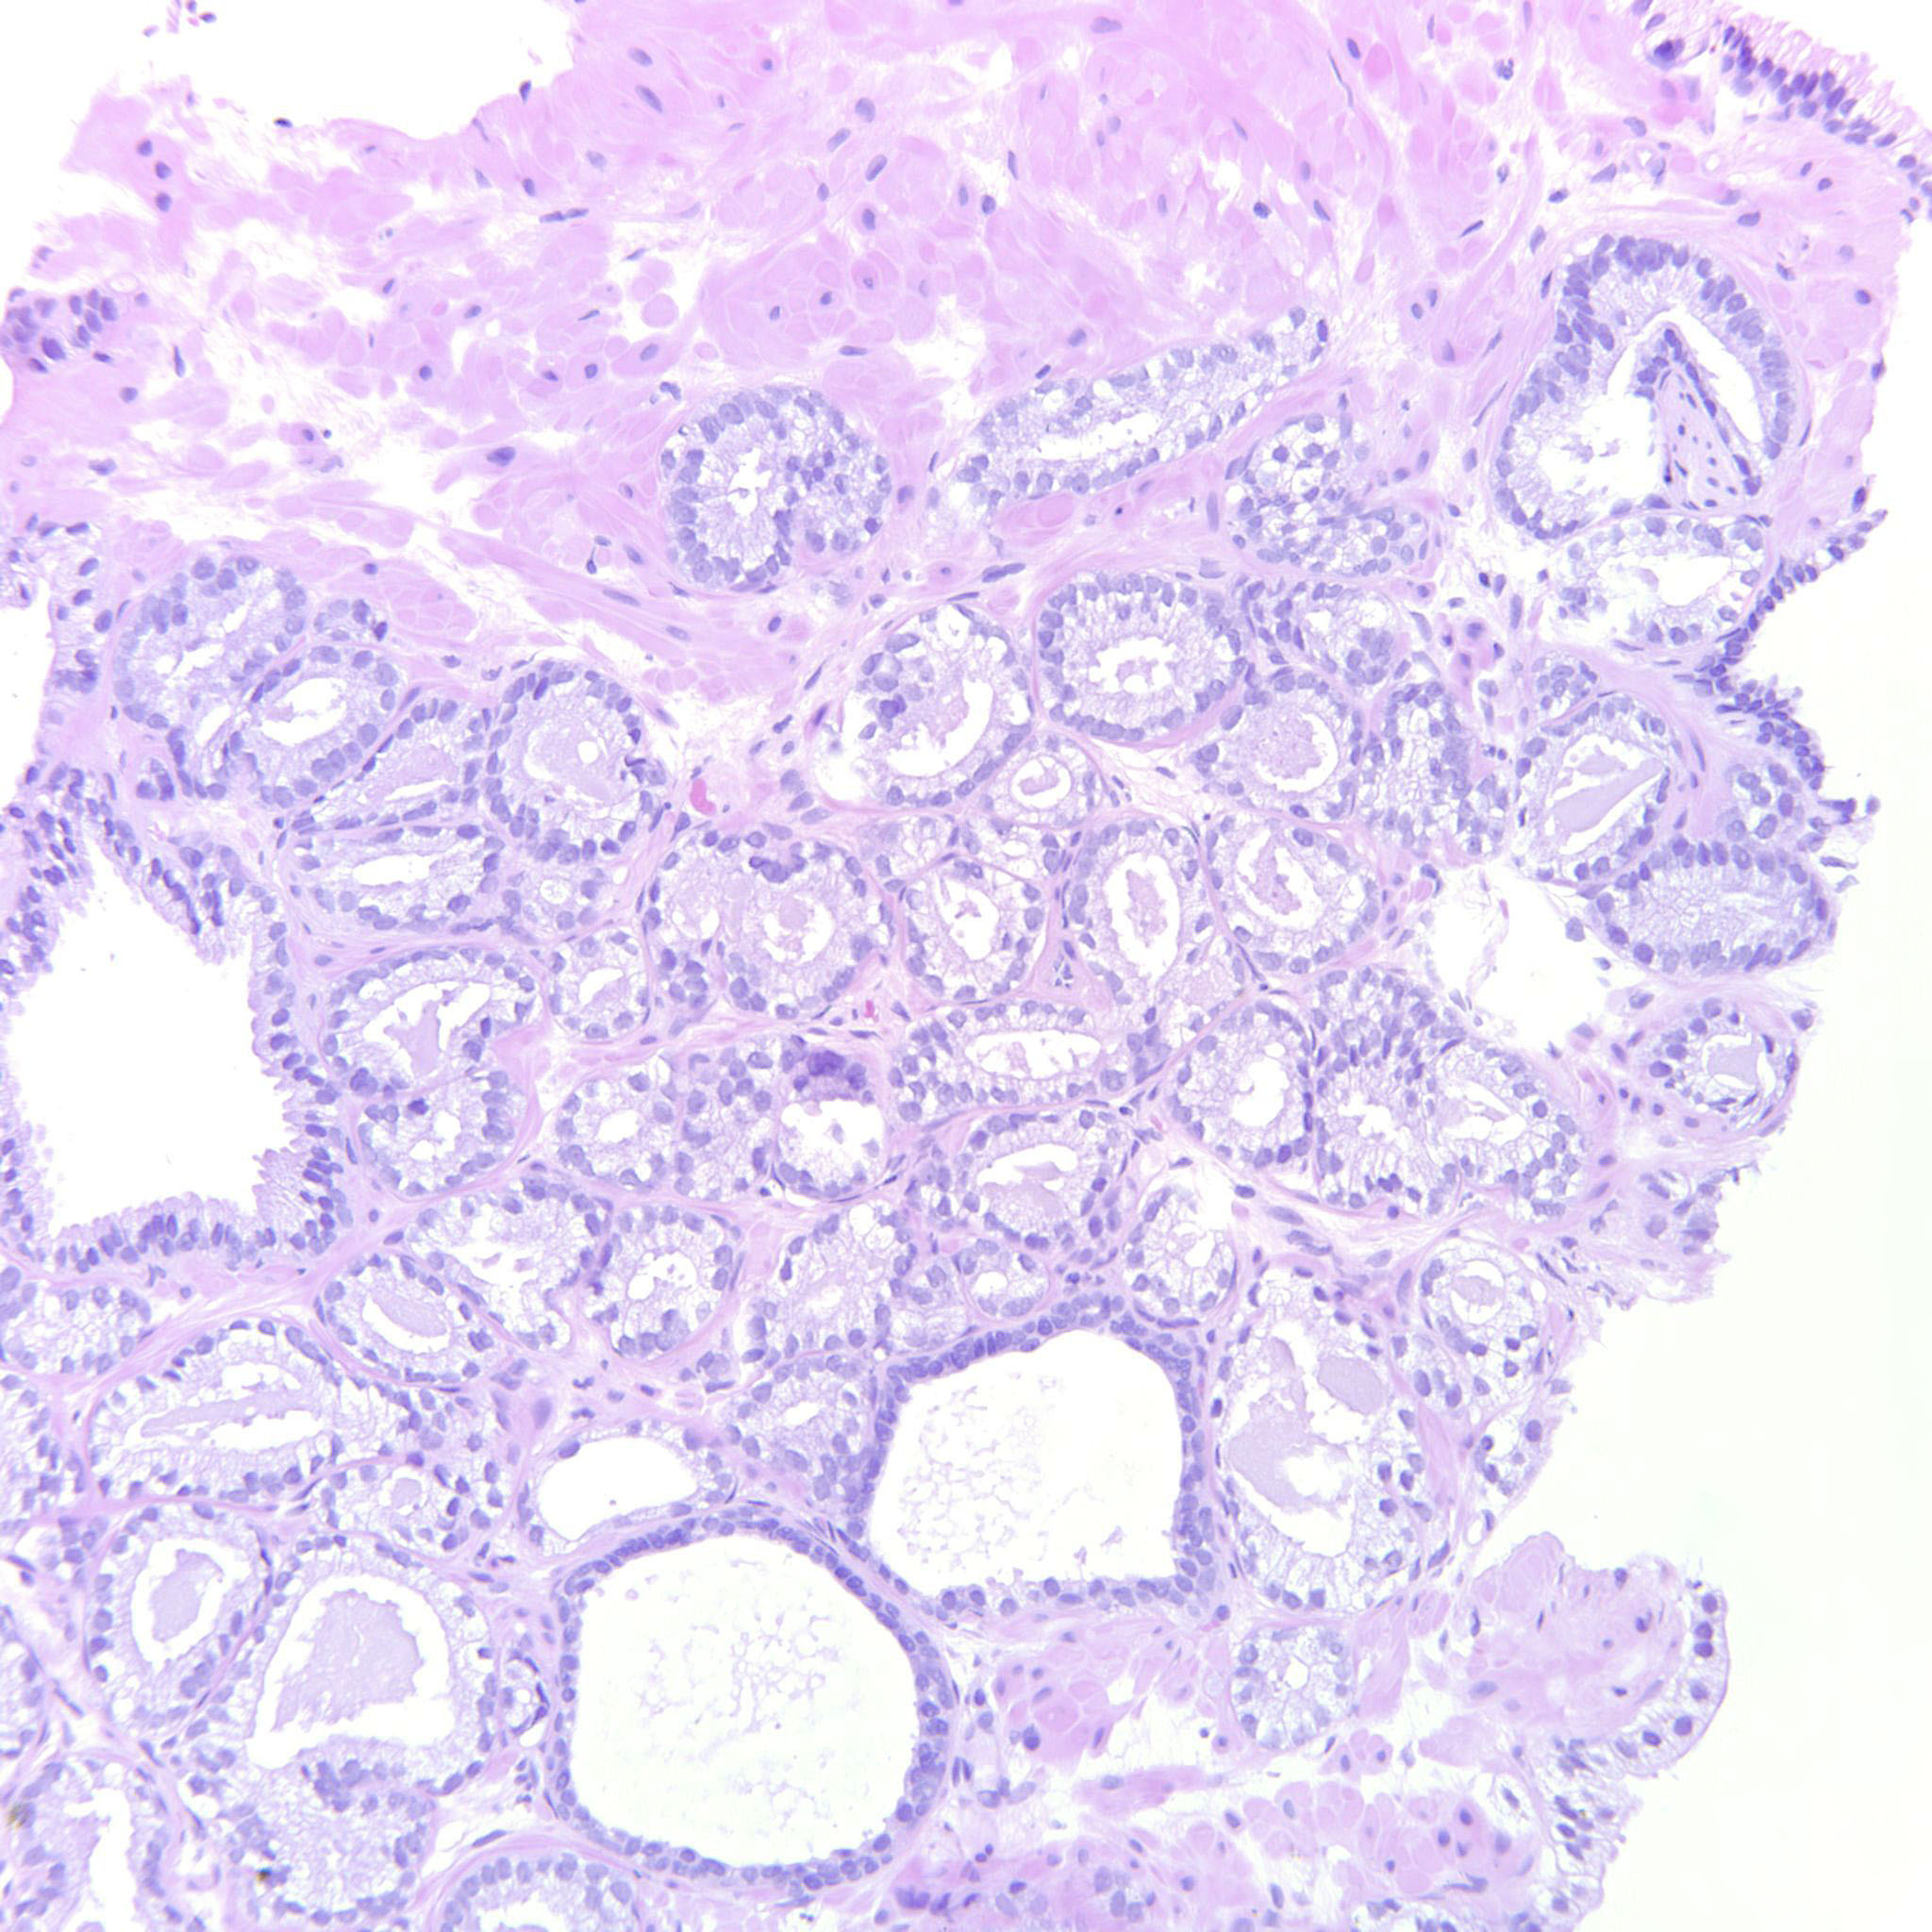

Prostate cancer grading

Case ID: 255